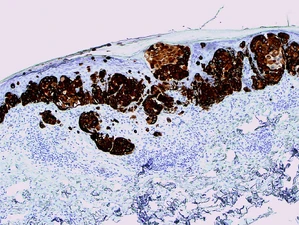

- If you have a good picture of what an immunostain should look like, PLEASE UPLOAD IT to that antibody's wiki page. Thanks for contributing to the Pathology Immunostain Wiki!

- HMB-45